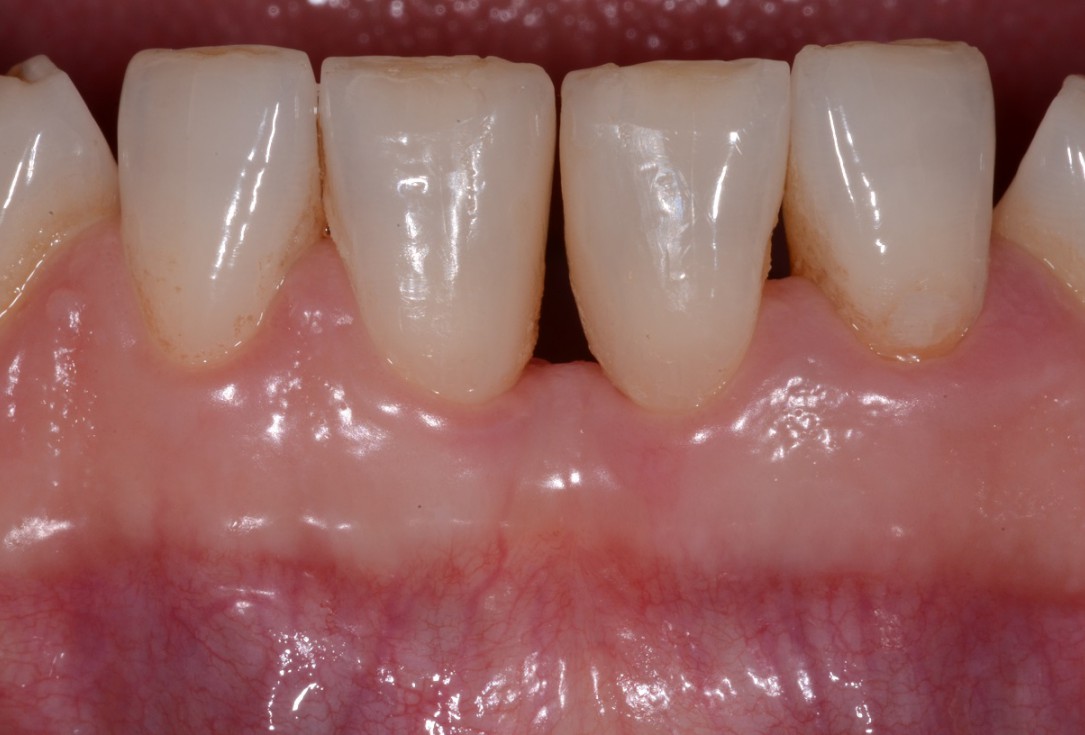

11/13 - Clinical situation 5 years post-operative.

Wide intrabony defect treated with the modified papilla preservation flap in conjunction with Straumann® Emdogain® and autogenous bone - Dr. B. Molnar